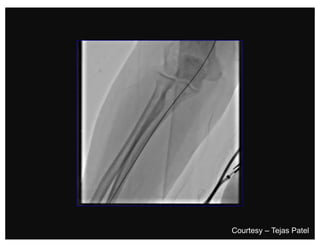

Traversing a radial loop

Brachial Tortuosity

Courtesy – Tejas Patel